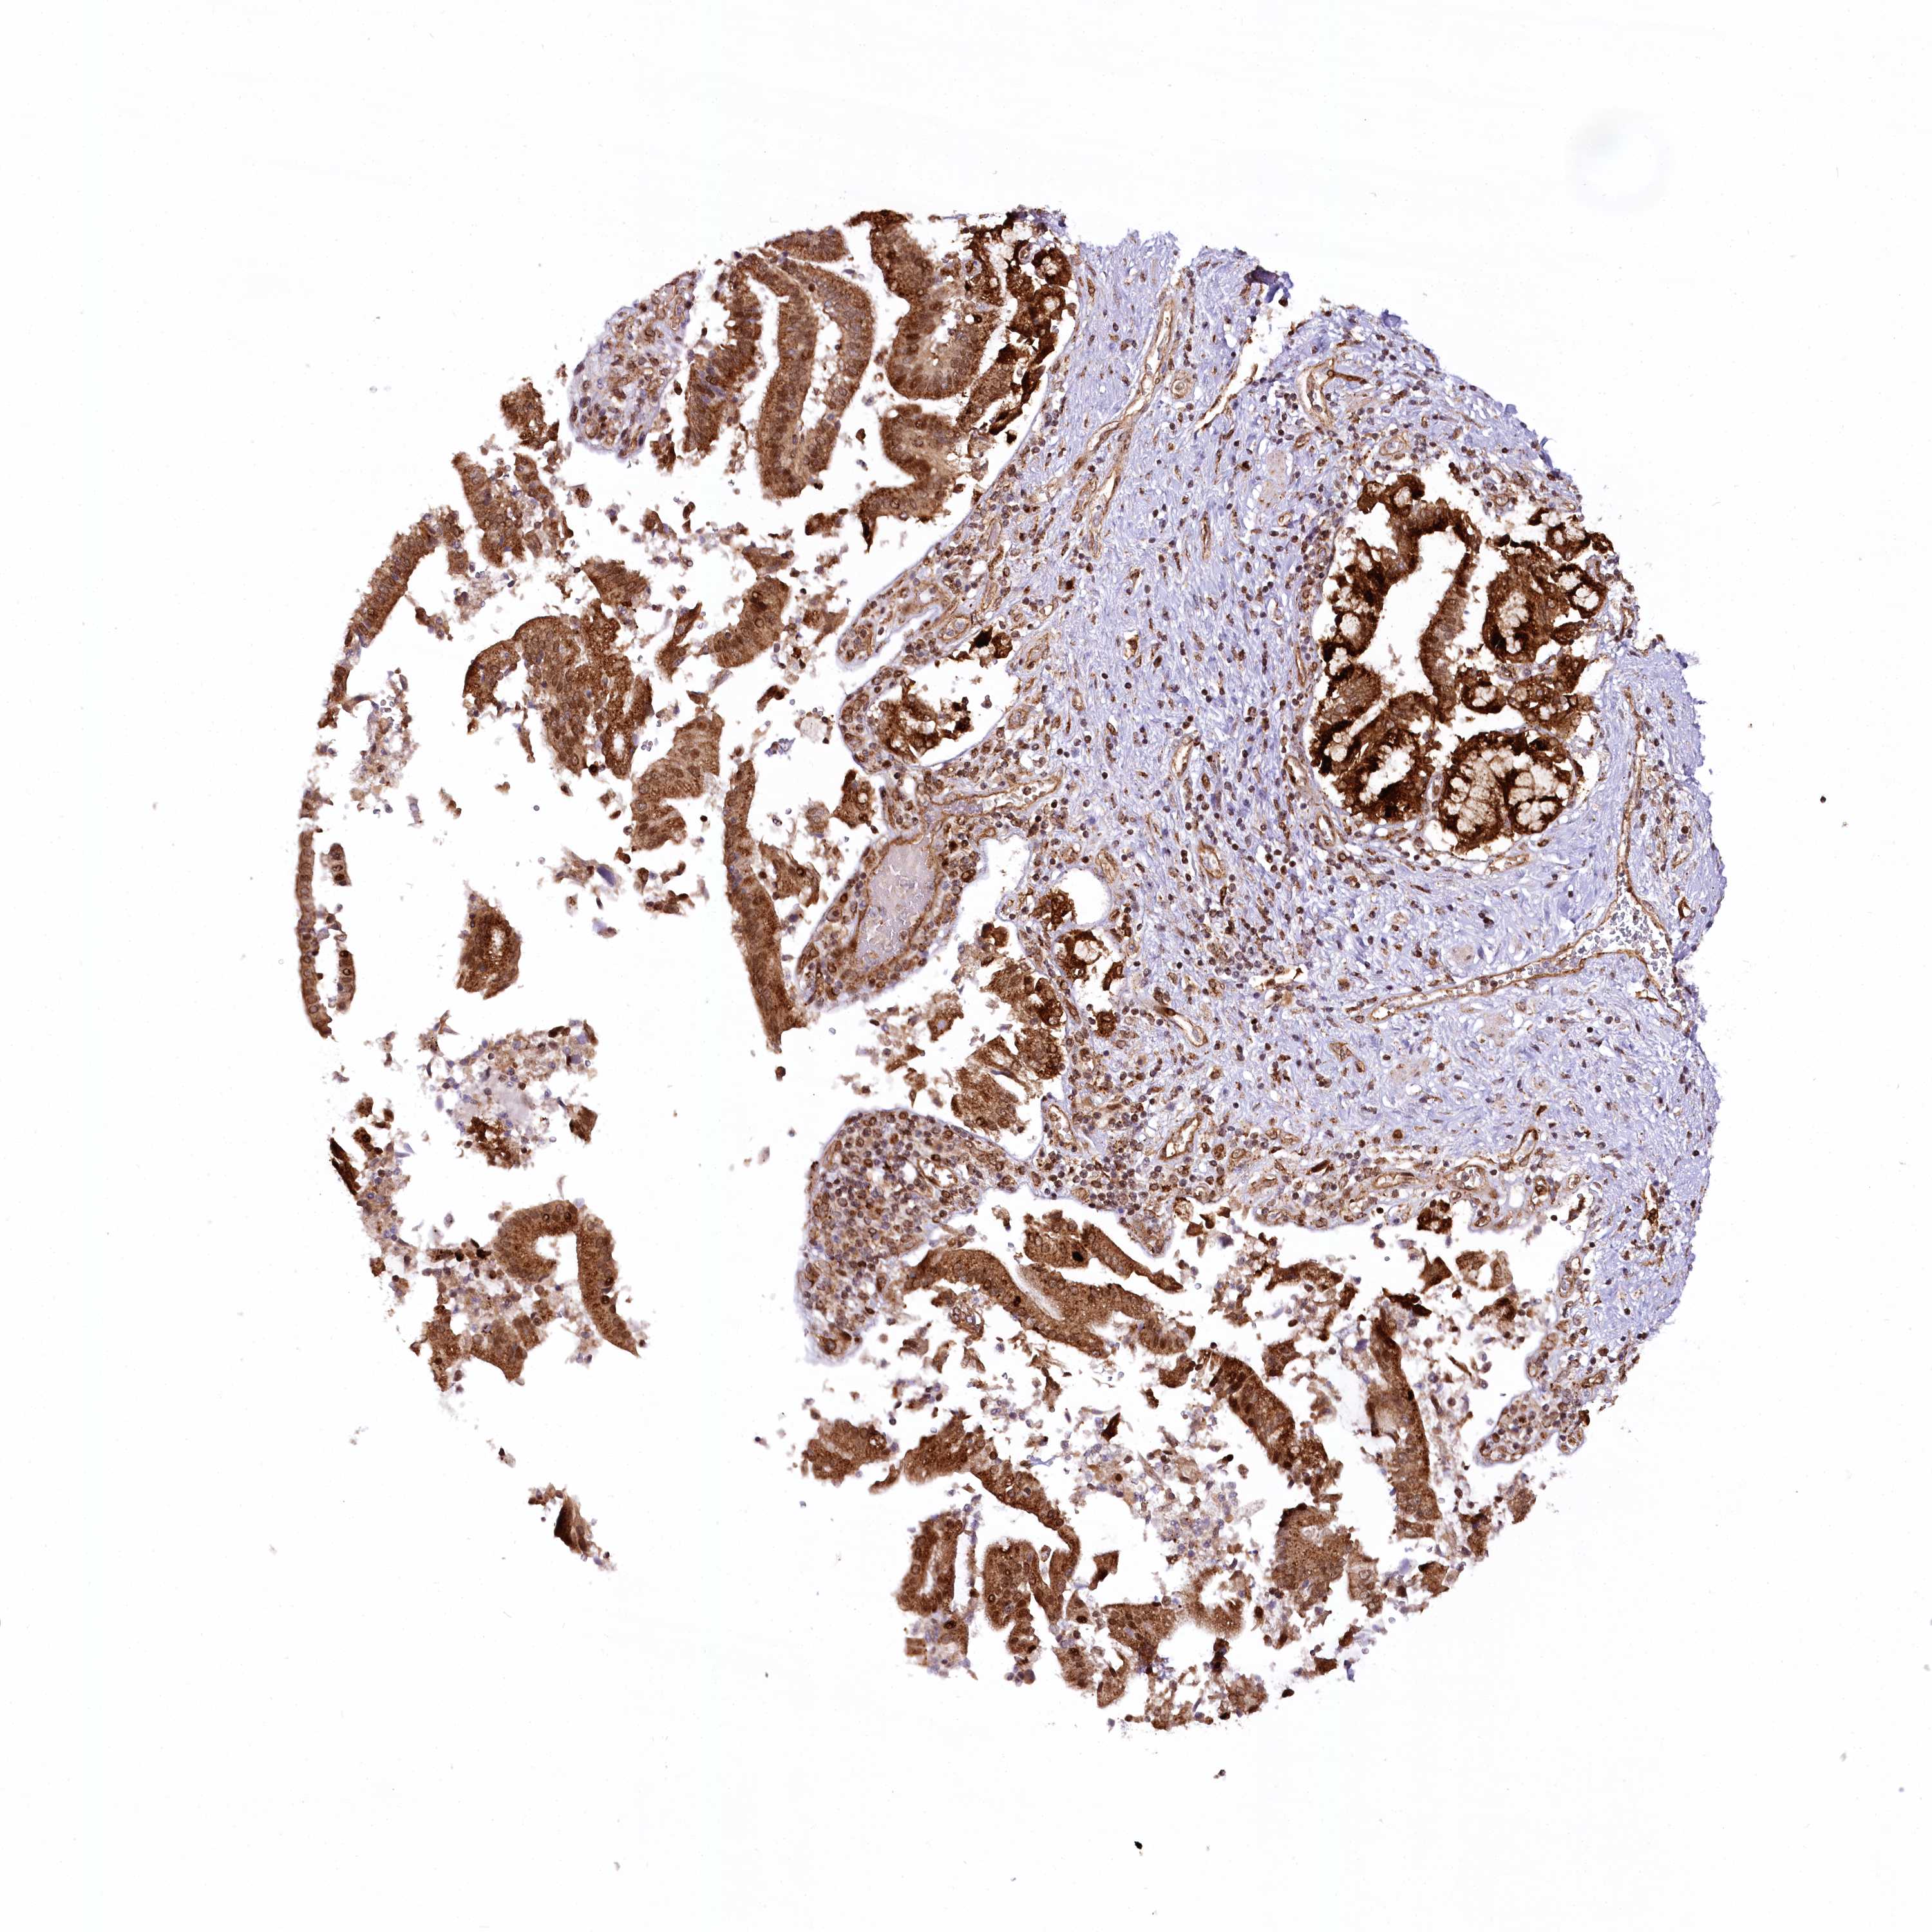

PANCREATIC CANCER - Protein expressioni

A mouse-over function shows sample information and annotation data. Click on an image to view it in a full screen mode. Samples can be filtered based on level of antibody staining by selecting one or several of the following categories: high, medium, low and not detected. The assay and annotation is described here.

Note that samples used for immunohistochemistry by the Human Protein Atlas do not correspond to samples in the TCGA dataset.

Antibody stainingi

Antibody staining in the annotated cell types in the current human tissue is reported as not detected, low, medium, or high, based on conventional immunohistochemistry profiling in selected tissues. This score is based on the combination of the staining intensity and fraction of stained cells.

Each image is clickable and will lead to virtual microscopy that enables deeper exploration of all samples and also displays staining intensity scores, fraction scores and subcellular localization as well as patient and tissue information for each sample.

Antibody HPA037866

Antibody HPA037867

Antibody HPA045712

Staining

High

Medium

Low

Not detected

Intensity

Strong

Moderate

Weak

Negative

Quantity

>75%

75%-25%

<25%

None

Location

Nuclear

Cytoplasmic/membranous

Cytoplasmic/membranous,nuclear

Adenocarcinoma, NOS